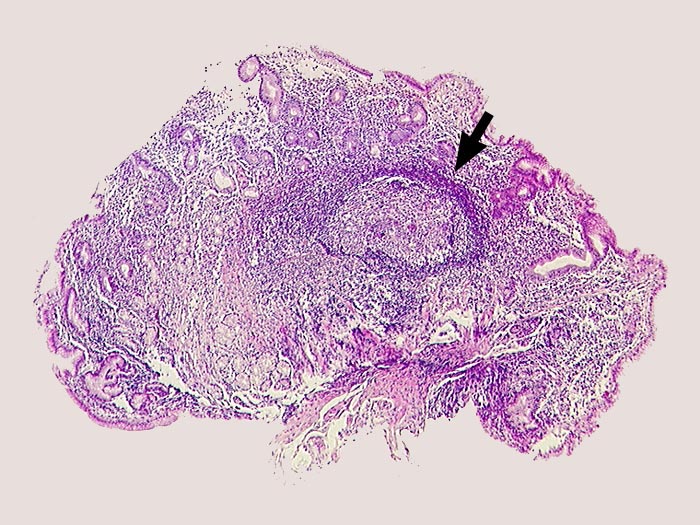

Schwere chronische Helicobactergastritis mit follikulärer Entzündung

Dichtes Entzündungsinfiltrat im Stroma. Lymphfollikel mit Keimzentrum.

Helicobacter.

Lymphfollikel kommen charakteristischerweise bei der Helicobactergastritis vor.